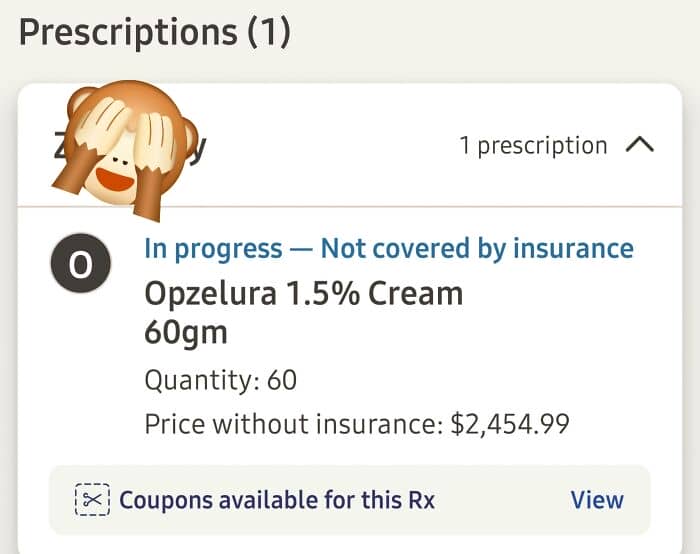

#57 That Price For The New Medicine My Doctor Says I Need